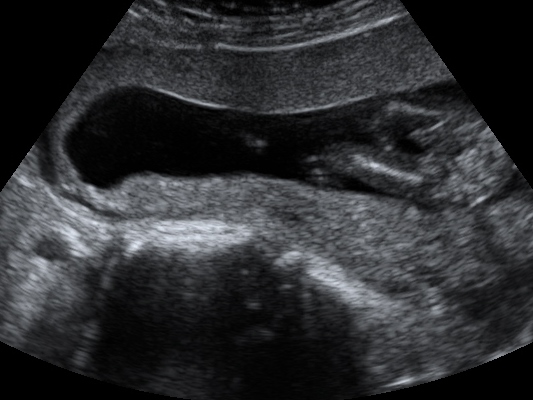

Tech was having a hard time and bouncing the wand on my belly to get baby to flip and move... but she said its a boy.

I was 15 weeks at this point

Was really hoping for a girl! :( Attachment 10463

I go back at 20 and can't help but hope that was the cord.

I just keep staring at the 2 little lines next to it and wondering what that is.

It looks very clearly scrotum and penis to me! Give yourself time to be excited! Boys are awesome :) you will see

The protrusion looks like a penis. I'm sorry you didn't hear girl.